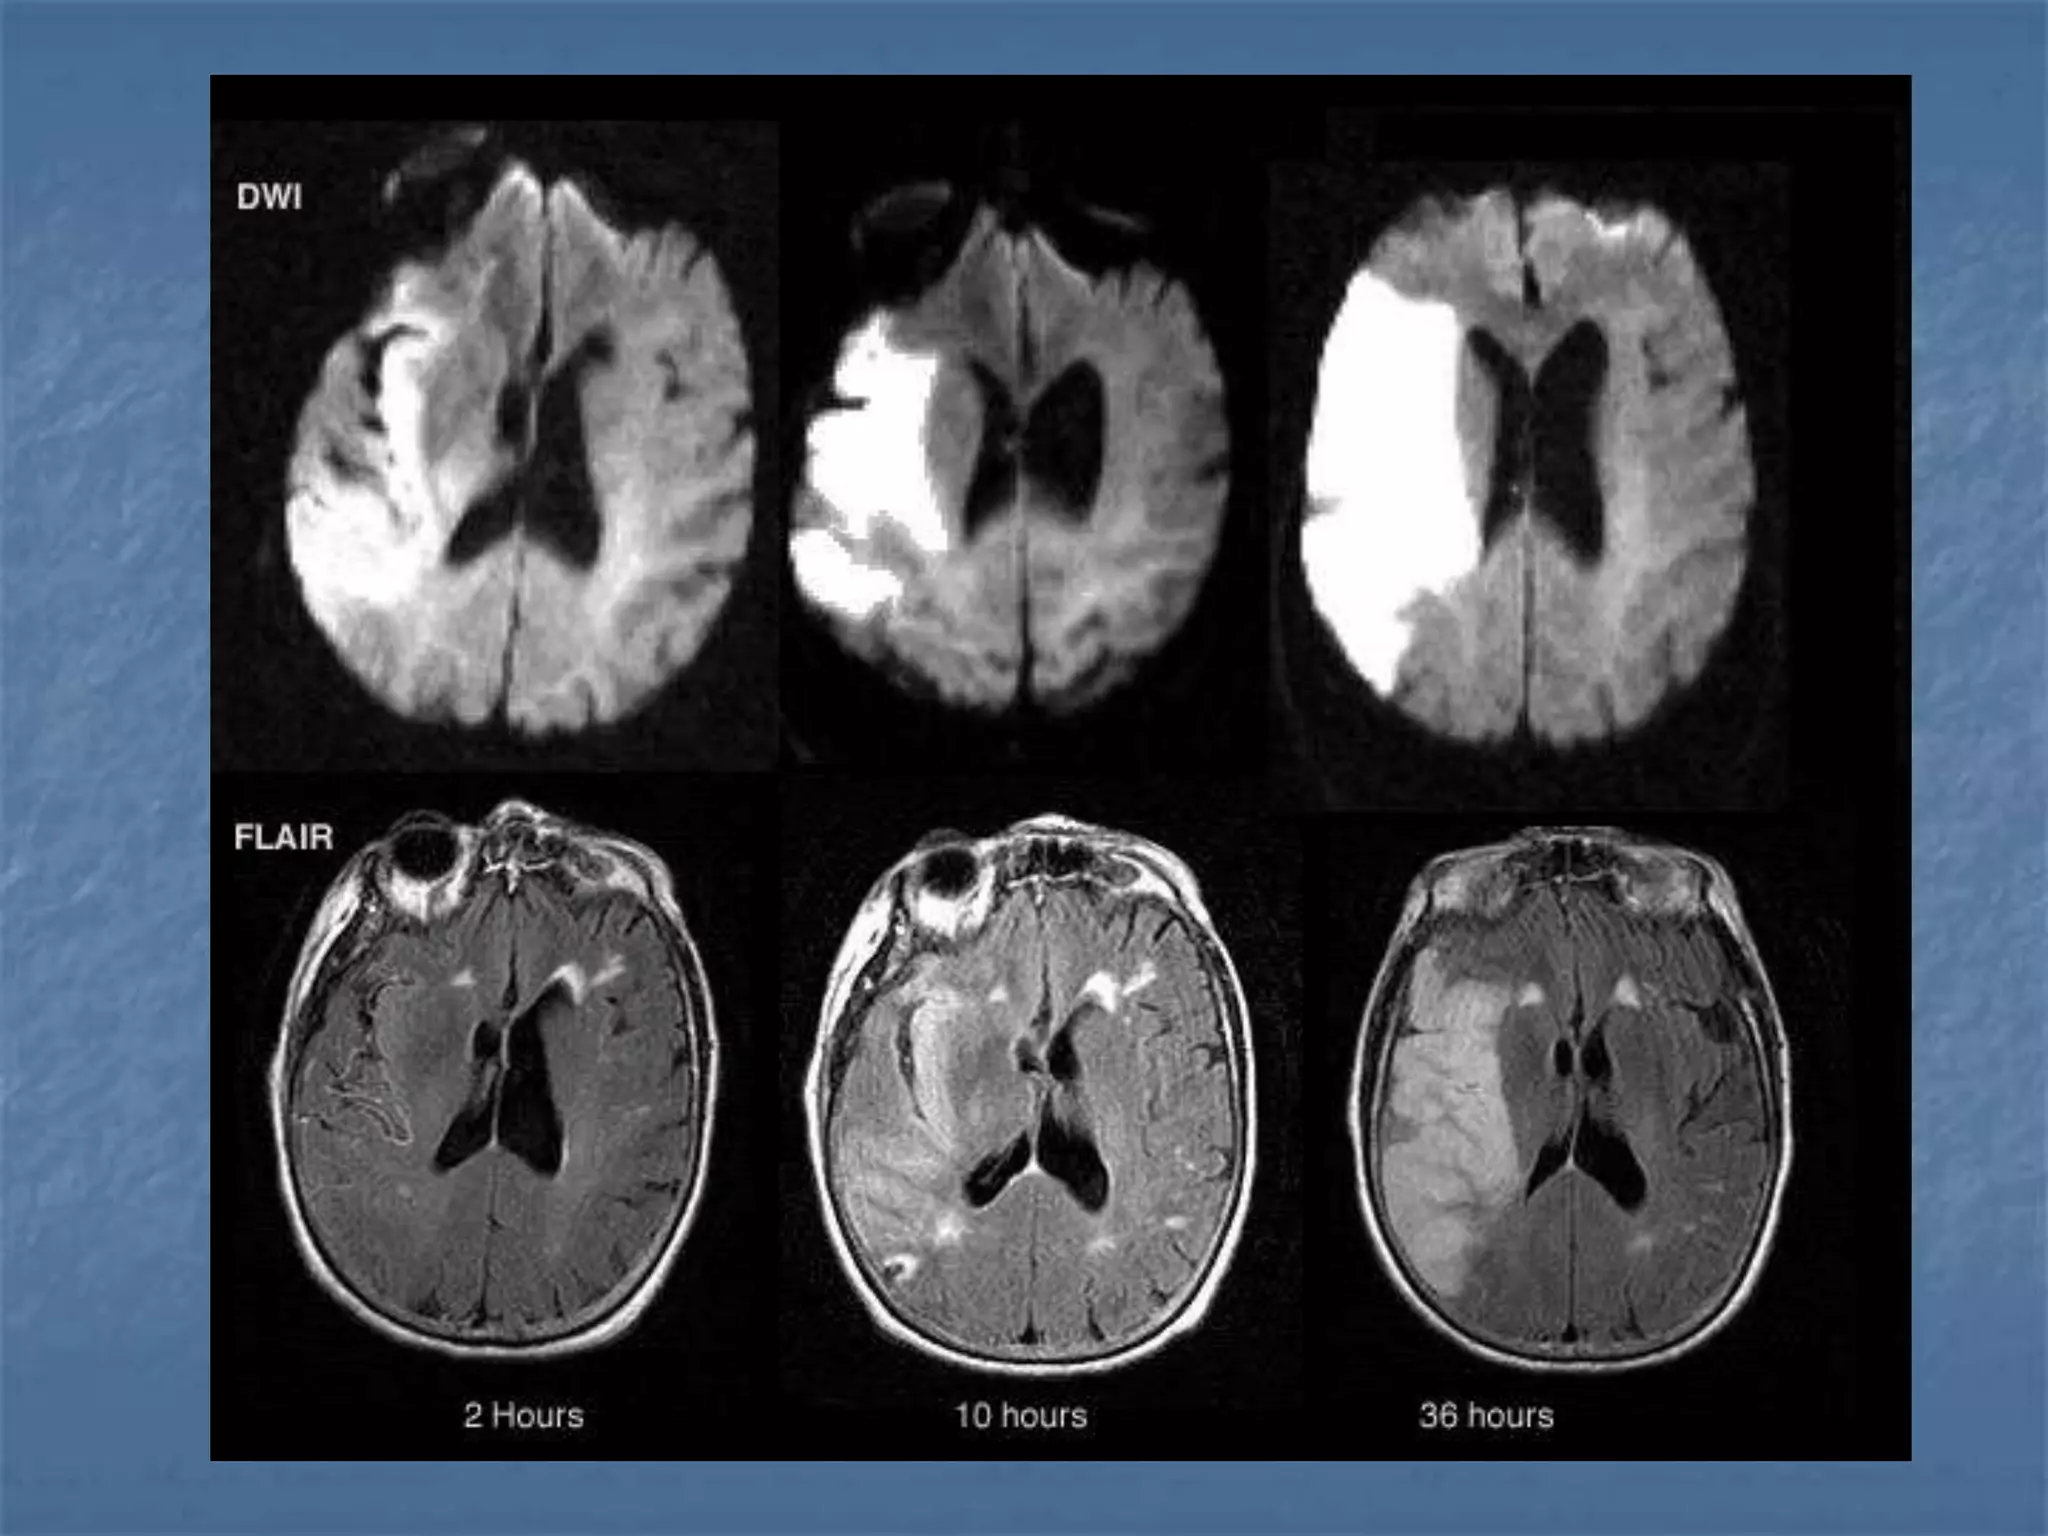

Diffusion Weighted Imaging

Radiology 2000;217:331-345

Detects Infarct As

Early As 15-30

minutes

AJNR 2003 ;24:878-885

• 46 patients with acute stroke

• CT and DWI within 6 hours

• Mean delay 24.5 min. (R 10–41 min.)

• EIC on CT - 33/46 (Sn 73%)

• DWI 42/45 - (Sn 93%)

 MRI has been increasingly utilized in

early stroke since it is more sensitive

than CT in the first twelve hours

 Bright on Diffusion weighted images

(detected as early as 15 to 30 min after

vessel occlusion).

MRI in Hyperacute Stroke

 DWI – Infarct core

 FLAIR - SAH , Parenchymal changes

 T2* GRE – Intracranial hemorrhage

 PWI – Perfusion deficit

 MRA – Vessel occlusion

 Sensitivity : 88 – 100 %

 Specificity : 95 – 100 %

 Initial diffusion lesion volume

correlates well with final infarct

volume & neurologic and functional

outcome

 Multiple a/c lesions in diff.vasc

territories in pts. with 1 symptomatic

insult …. embolic